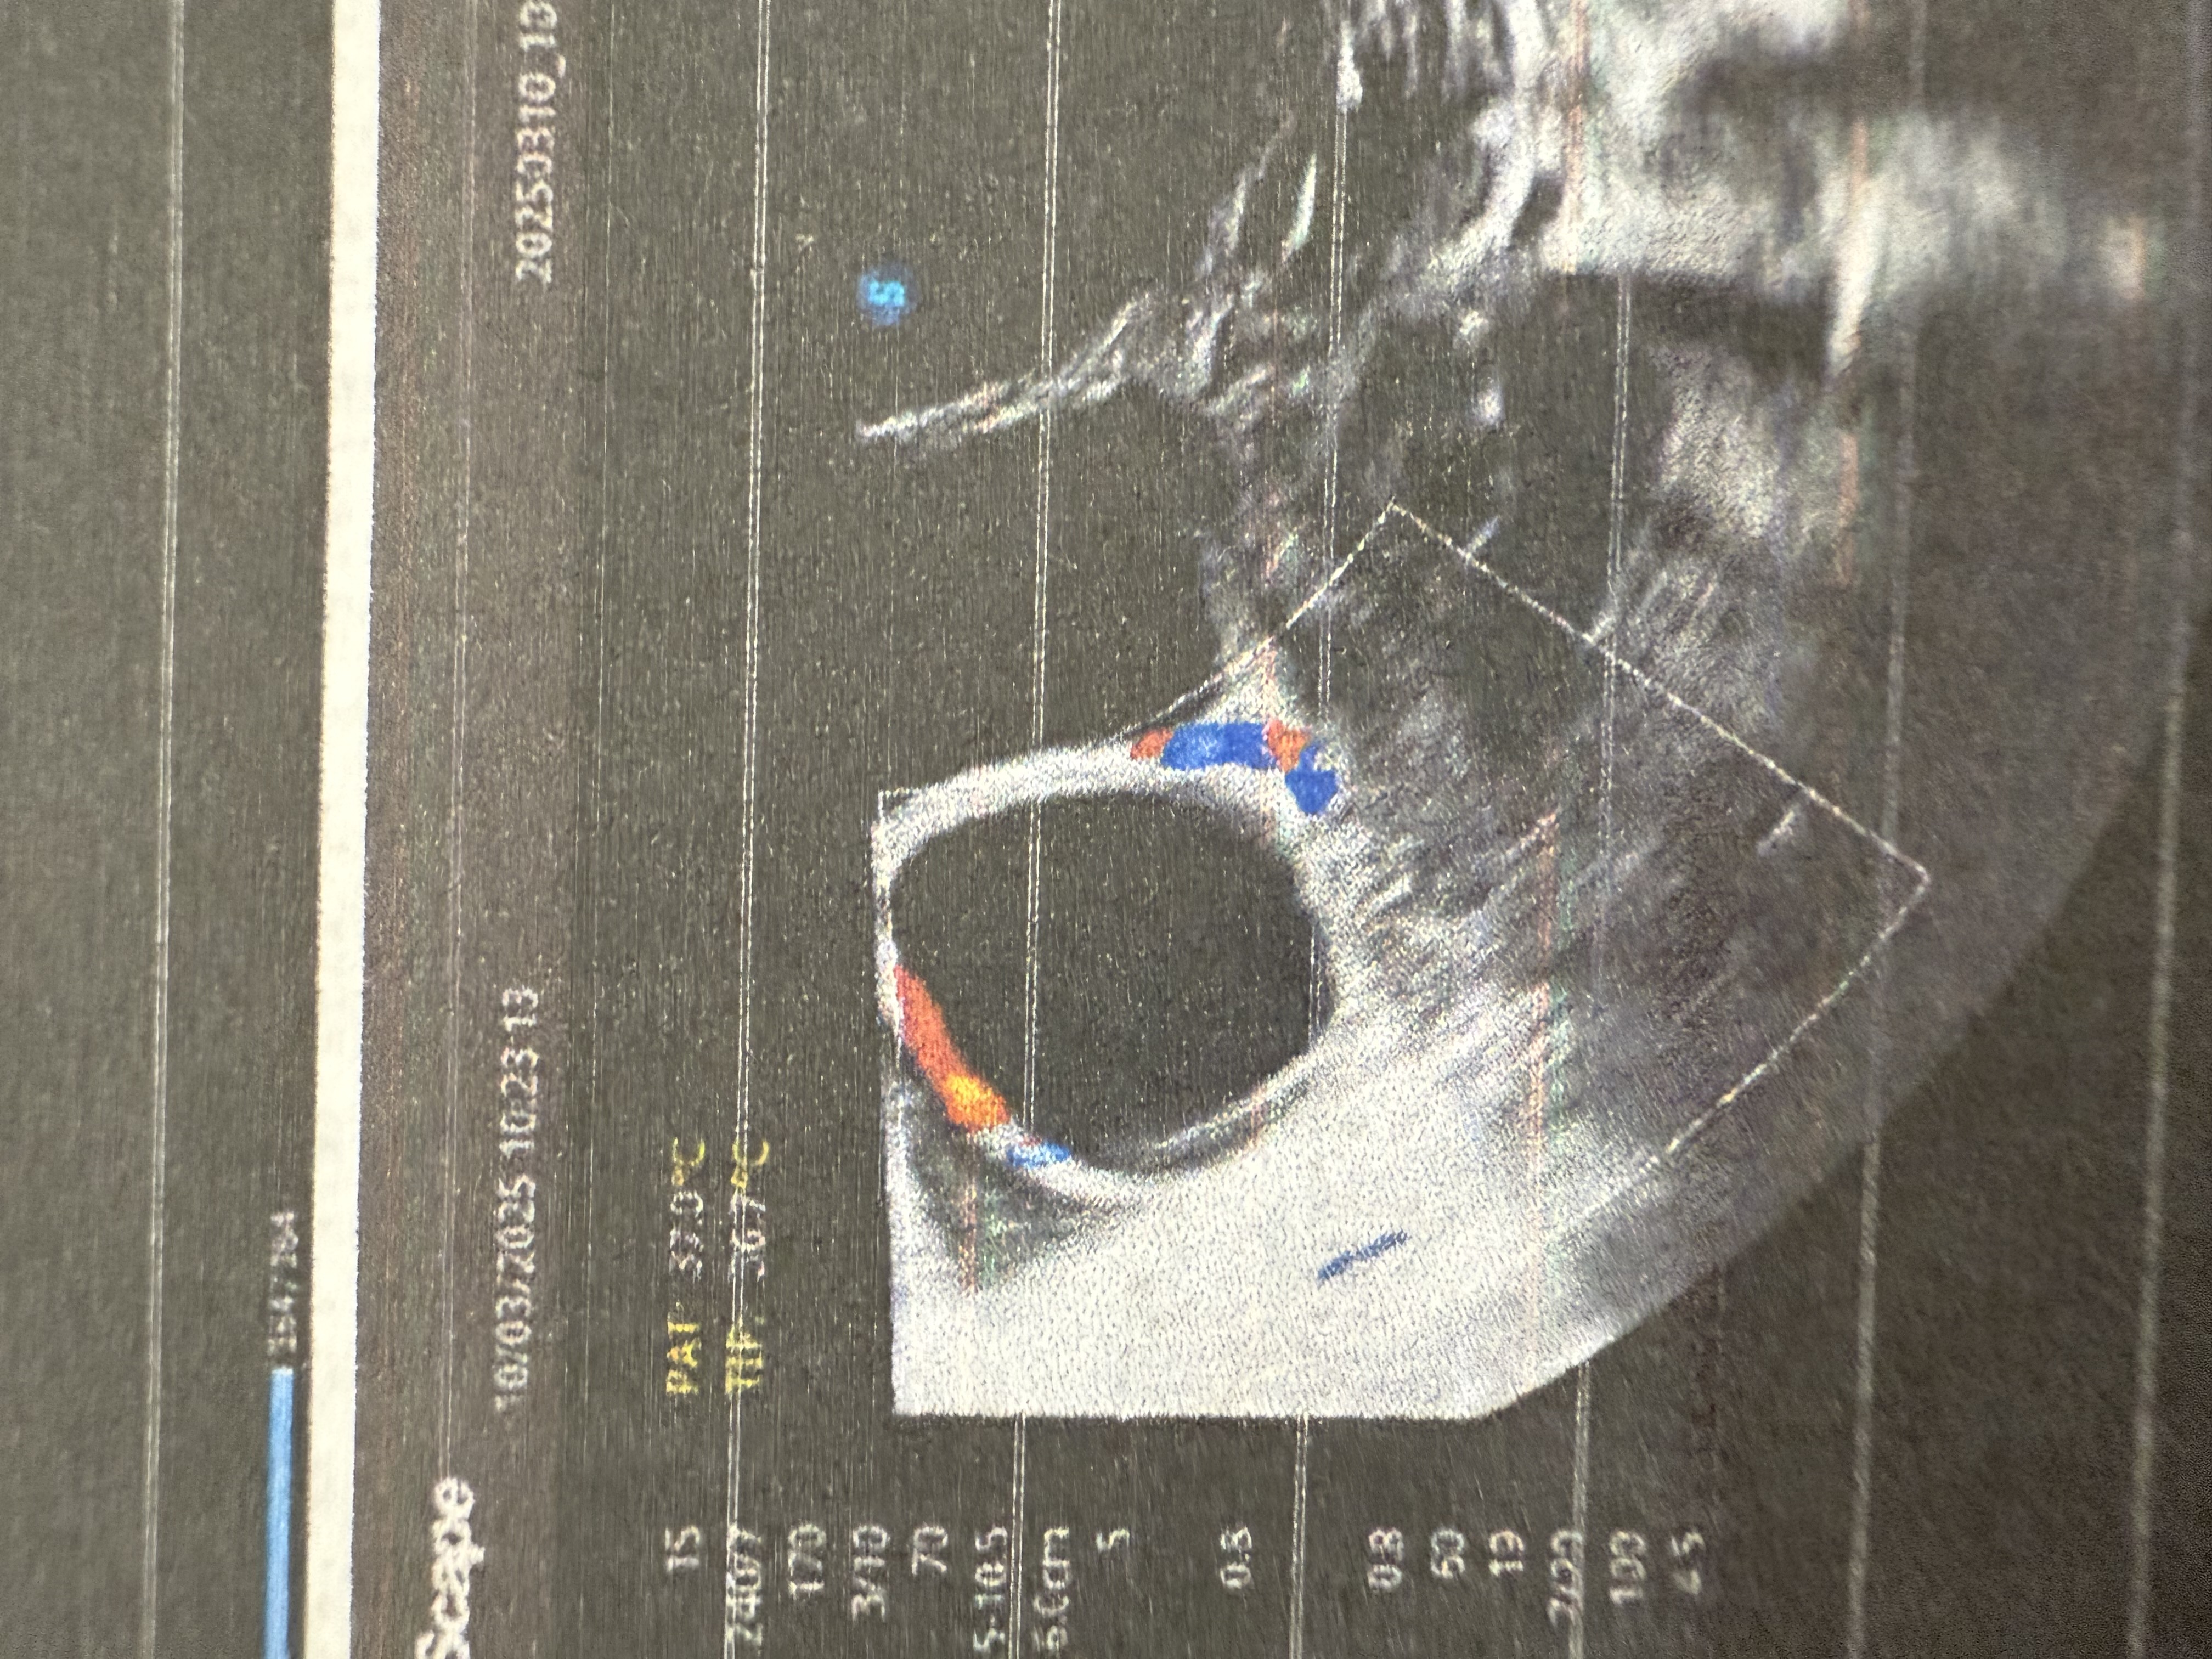

Фолликул сразу после овуляции

фолликул слева 22х20 мм (сказала что скорее всего уже не совулирует)

желтое тело слева 22х20 мм (сказала что овуляция была совсем недавно)

меня смущает то, что жт сразу такое большое и с ровными четкими контурами. Переспросила у узистки. Она сказала, что после овуляции вокруг совулировавшего фолликула есть жидкость. Это говорит о том, что фолликул лопнул и с него вышла жидкость. У меня как раз в этой области жидкость + еще в позадиматочном пространстве.

я думала, что сразу после овуляции фолликул сначала сдувается, и становится как будто сморщенный. А у меня прям сразу с четкими контурами и достаточно большой, думала что он уже потом во второй фазе растет уже как жт.

Алтыша, справа вверху уже не ровный край, похже вот вот была О , через пару дней переделайте фалекулометрию, уже будет нормальное ЖТ, может ещё и второй лопнет сегодня.

Овулирующий фолликул будет такой же, только с не ровными очертаниями.

А если жёлтое тело есть, значит овуляция была.